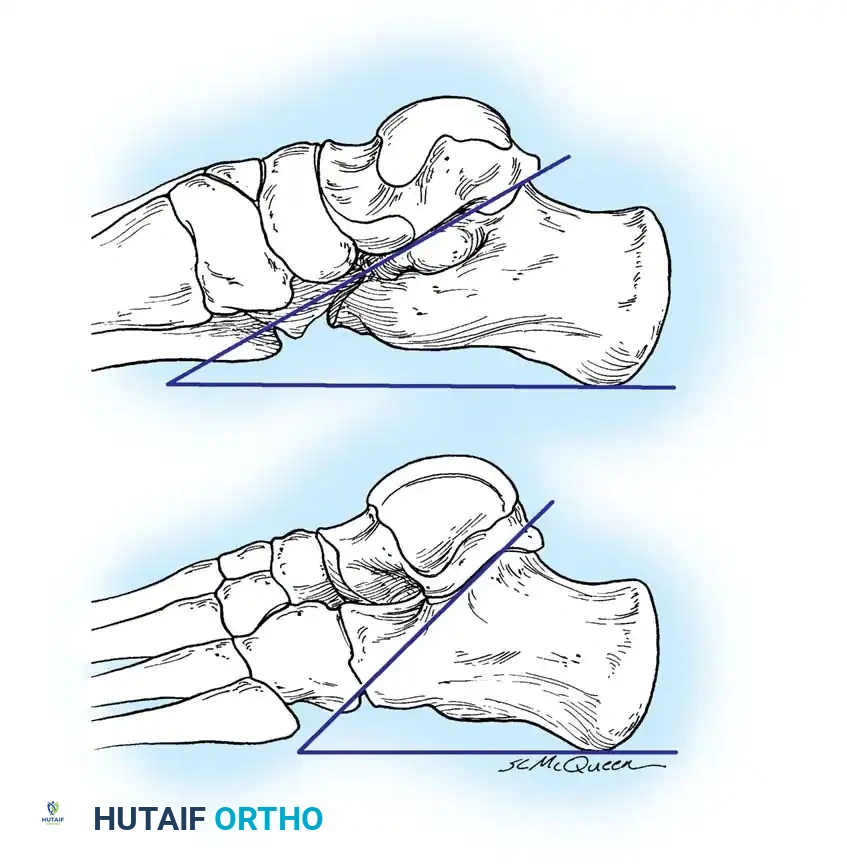

يعتمد التشخيص الدقيق على الجمع بين الفحص السريري الدقيق والتصوير الطبي المتقدم، حيث يقوم طبيب العظام المتخصص بتقييم حالة المريض بشكل شامل.

الفحص السريري

يقوم الطبيب بفحص مشية المريض، وتقييم شكل قوس القدم أثناء الوقوف. الأهم من ذلك هو فحص مدى حركة المفصل تحت الكاحل (Subtalar Joint). في حالة القدم المسطحة الصلبة، تكون الحركة مقيدة بشدة أو معدومة تماماً. قد يلاحظ الطبيب أيضاً تشنجاً في العضلات عند محاولة تحريك القدم بقوة.

القدم المسطحة المرنة يظهر فيها قوس القدم عند الوقوف على أطراف الأصابع أو عند عدم تحميل الوزن، ونادراً ما تسبب ألماً. أما القدم المسطحة الصلبة (Rigid Pes Planus) فتكون قاسية، ولا يظهر القوس في أي وضعية، وغالباً ما تكون مصحوبة بألم وتصلب يتطلب تدخلاً طبياً.